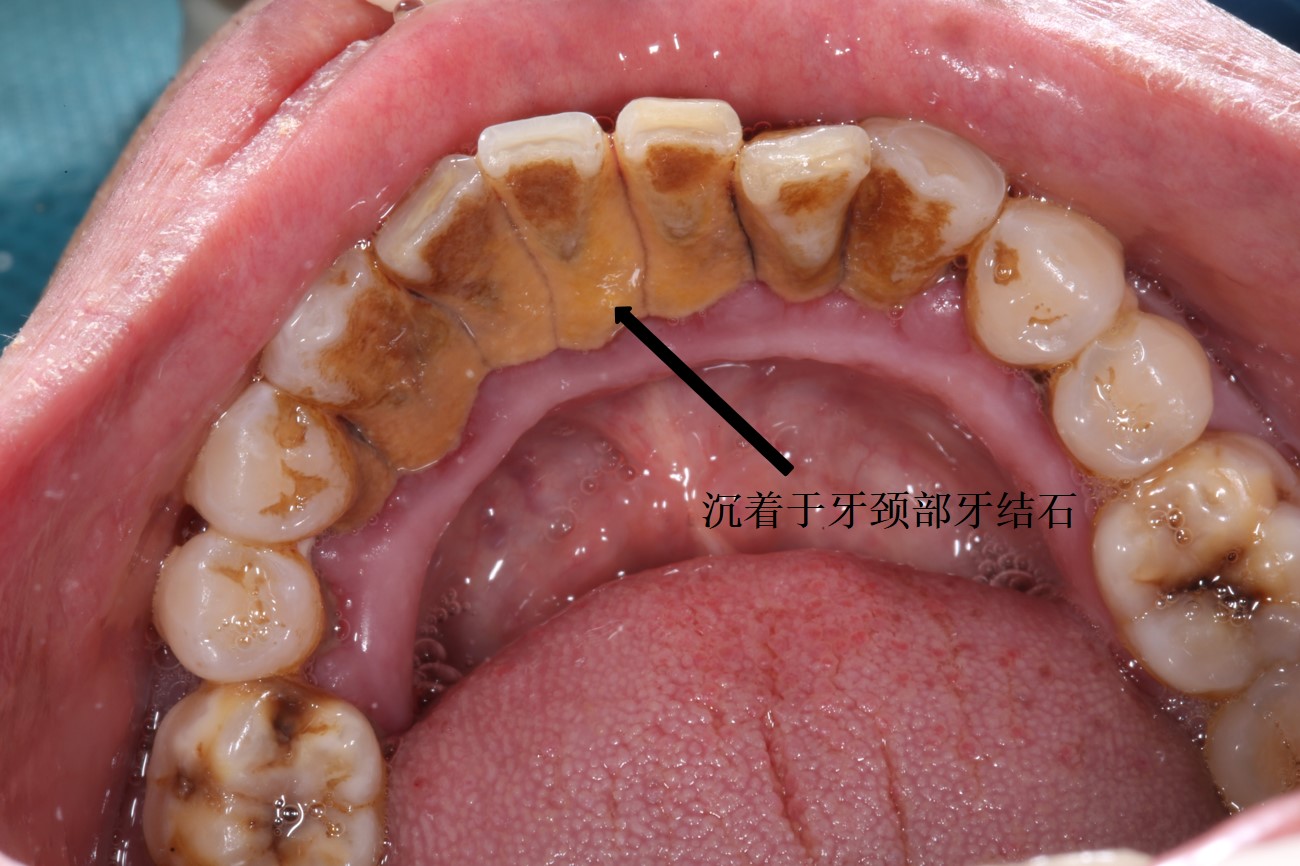

这是为什么呢?原因在于很多患者刷牙次数少,或者是刷牙的清洁效率不高,导致牙结石沉积于牙齿周围。牙结石是由食物残渣、坏死细胞及唾液中的矿物质钙化后附着在牙齿表面形成的矿化结石。其表面粗糙,容易堆积各种菌斑,吸附细菌产生的大量毒素,刺激牙龈发炎,处于红肿状态,轻微的机械刺激,就会导致牙龈出血。牙结石一旦形成,刷牙已经不能够有效清除,必须通过机械清洗的办法去除。临床牙医称之为超声洁牙,患者更多称之为“洗牙”。

牙结石形成仅需要十二至十五小时,一般情况下建议每半年到一年洗一次牙。牙结石一旦形成,刷牙已经不能够有效去除,必须是临床牙医通过机械的方法去除,如超声波洗牙。另外在洗牙的过程中,牙医会对您的整体口腔状况做出正确的判断,也是一次全面的口腔检查,做到牙病早发现、早诊断、早治疗。